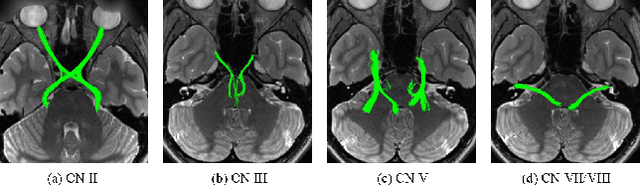

Abstract:Diffusion MRI tractography is an important tool for identifying and analyzing the intracranial course of cranial nerves (CNs). However, the complex environment of the skull base leads to ambiguous spatial correspondence between diffusion directions and fiber geometry, and existing diffusion tractography methods of CNs identification are prone to producing erroneous trajectories and missing true positive connections. To overcome the above challenge, we propose a novel CNs identification framework with anatomy-guided fiber trajectory distribution, which incorporates anatomical shape prior knowledge during the process of CNs tracing to build diffusion tensor vector fields. We introduce higher-order streamline differential equations for continuous flow field representations to directly characterize the fiber trajectory distribution of CNs from the tract-based level. The experimental results on the vivo HCP dataset and the clinical MDM dataset demonstrate that the proposed method reduces false-positive fiber production compared to competing methods and produces reconstructed CNs (i.e. CN II, CN III, CN V, and CN VII/VIII) that are judged to better correspond to the known anatomy.